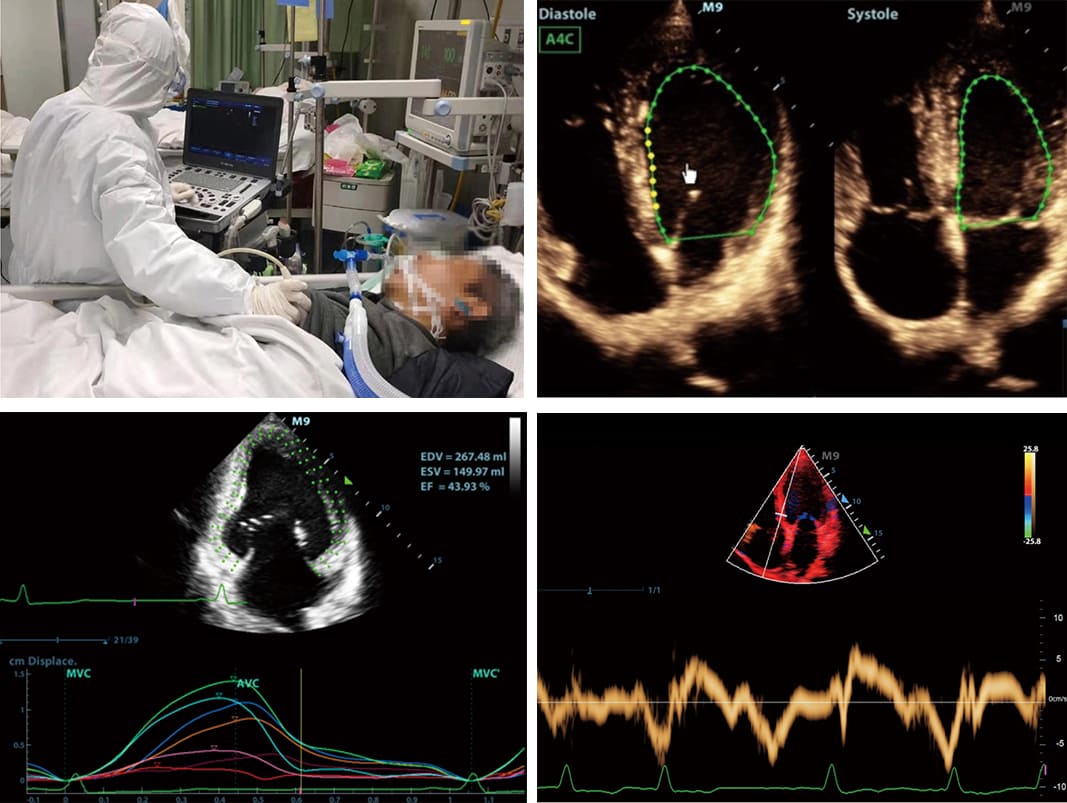

4. Cardiac Disease Assessment

One of the most compelling applications of portable ultrasound in critical care is the assessment of cardiac function. These devices support automatic measurement of cardiac function, making it easier for clinicians to diagnose and monitor cardiac conditions. They also offer advanced features such as TDI tissue Doppler assessment of diastolic function and tissue spot tracking assessment of cardiac machine movement. These capabilities empower clinicians to make informed decisions, especially in situations where time is of the essence.